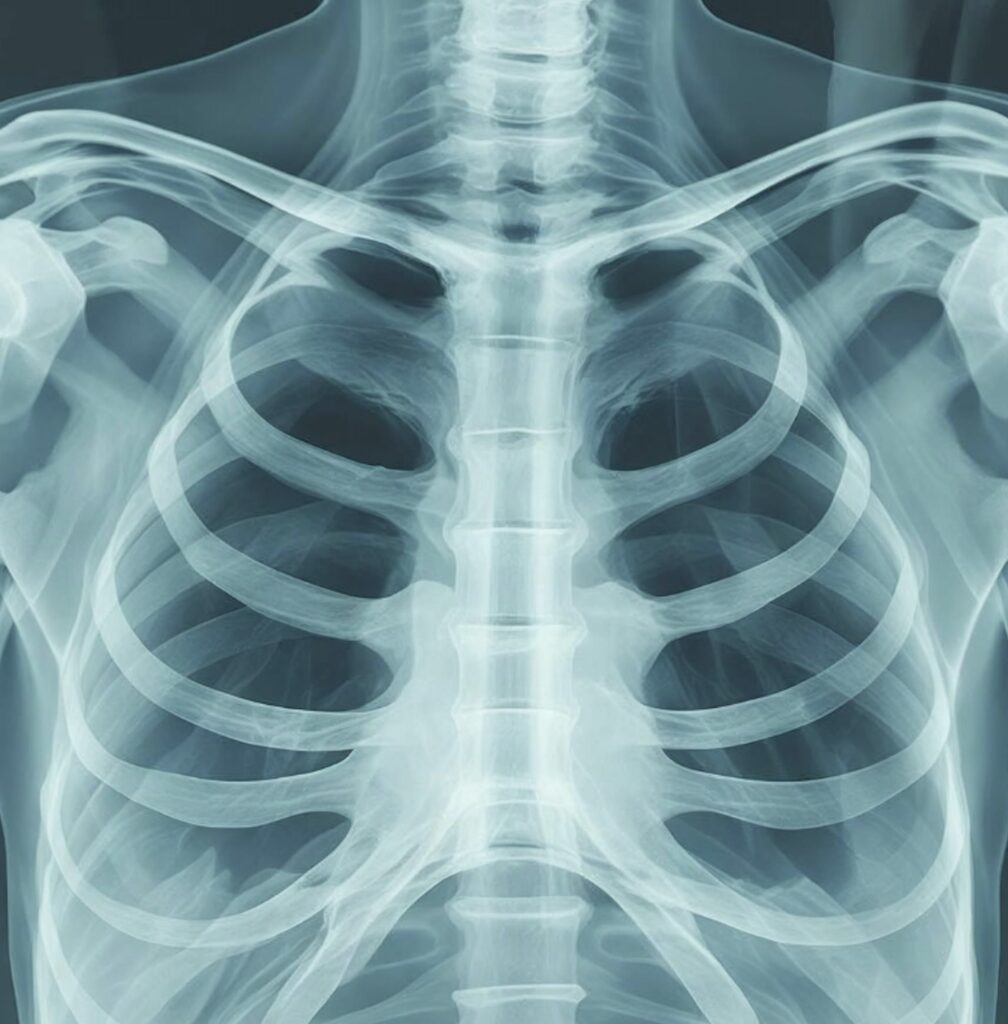

At Harley Longevity Club, we offer the DEXA scan, a highly accurate, non-invasive imaging test that measures your body composition in detail. It goes beyond standard weight or BMI by providing precise insights into your bone density, muscle mass, and body fat distribution. This allows you to better understand your overall health, track changes over time, and make more informed decisions about fitness, nutrition, and long-term wellbeing.